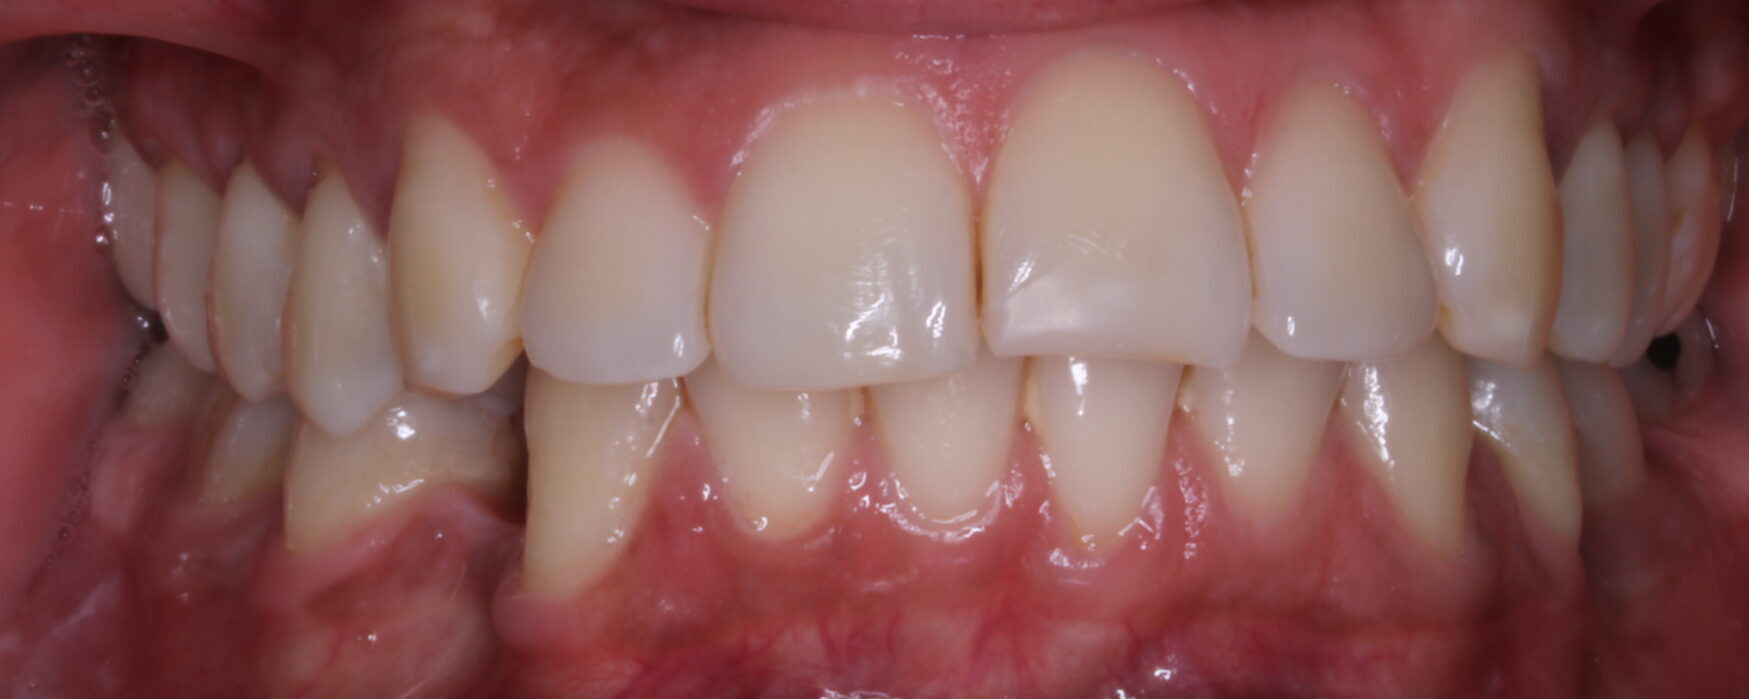

FOTOGRAFÍAS DE INTERÉS